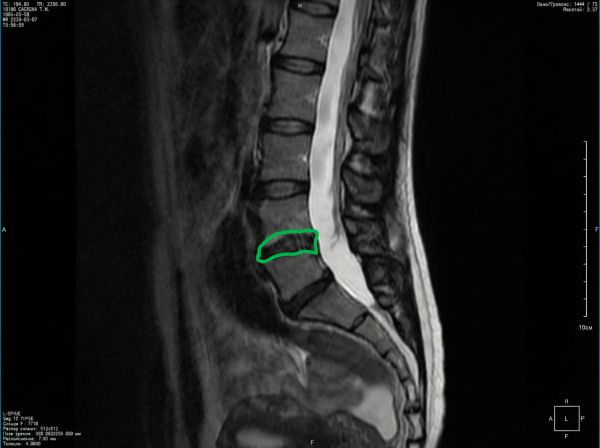

Пациентка, 40 лет. Грыжа позвоночника, 2 сантиметра.

Грыжи нет, остался только рубец.